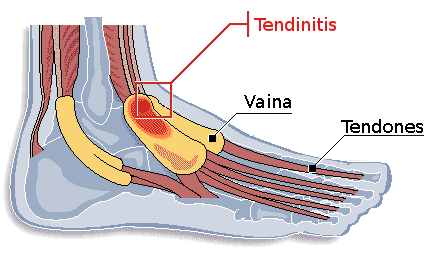

La tenosinovitis es una inflamación del revestimiento de la vaina que rodea al tendón y puede ser incapacitante por el dolor que puede conllevar en pies y manos.

Imagina un tendón que es aquello que un músculo de nuestra mano con el hueso y que a su vez tiene un revestimiento que es la membrana sinovial que protege y aísla los tendones. Es aquí donde se produce la inflamación y el dolor.

En los movimientos repetitivos hay excesiva fricción del tendón con el hueso y por ello hay desgaste y lesiones en la vaina que rodea los tendones para dar paso a la inflamación.